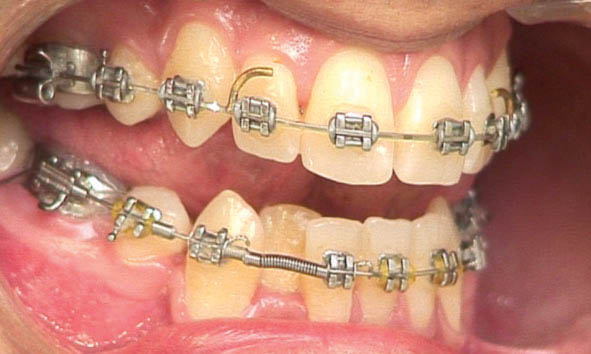

اگر فاصله هوکهای خلفی و قدامی تا 18 میلیمتر است از طول 9 میلیمتر مدیوم و اگر بیشتر بود از طول 12 میلیمتری مدیوم آن استفاده میکنیم (شکل 183-1). معمولاً این فنرها را حداکثر تا دو و نیم برابر طول خودشان میتوانید بکشید.

شکل 183-1: قراردادن فنر کلوز بین هوک خلفی و قدامی باعث بسته شدن فضا میشود.

در بیماران به روش کشیدنی با استفاده از laceback دندان كانین را به دیستال حركت میدهیم تا فضا برای لترال پالاتالی فراهم شود. حركت دیستالی كانین باعث حركت مزیالی دندان 5 و 6 میشود. اگر حركت مزیالی دندان 6 مطلوب نباشد و هم چنین پروترود شدن سانترال نیز مد نظر باشد (اصلاح میدلاین یا اضافه کردن اورجت) به جای استفاده از laceback، از فنر استفاده میكنیم تا باعث جلو آمدن سانترال و عقب رفتن کانین به طور همزمان شود (شکل 185-1). به هنگام استفاده از فنر معمولاً

bendback نمیزنیم (خم کردن سیم در انتهای تیوب مولر دوم) تا فضا سریعتر باز شود.

با گذاشتن فنر باز بین براکتهای سانترال و کانین برای لترال فضا ایجاد میشود (شکل 185-1). برای این منظور مقداری از فنر open را (30 درصد بیشتر از فاصله دو براکت) بریده و آرچوایر را از درون آن رد میکنید. بعد از جا گذاری به علت فشرده شدن باعث اعمال نیرو شده و دو دندان سانترال و کانین را از هم دور میکند. اگر bendback زده باشید، فقط کانین عقب میرود اما اگر bendback نزده باشید هم کانین عقب میرود و هم سانترال جلو میآید. در صورتی که بین دو سانترال فضا باشد ابتدا فضا بسته میشود بعد سانترالها پروترود میشوند (و بدیهی است که اگر یکطرفه فنر گذاشته باشید مقداری میدلاین به سمت دیگر حرکت میکند).

شکل 185-1: بعد از مرتب شدن تمام دندانها به غیر از لترال، فنر باز بین براکت سانترال و کانین قرار میدهیم تا فضا برای لترال ایجاد شود.